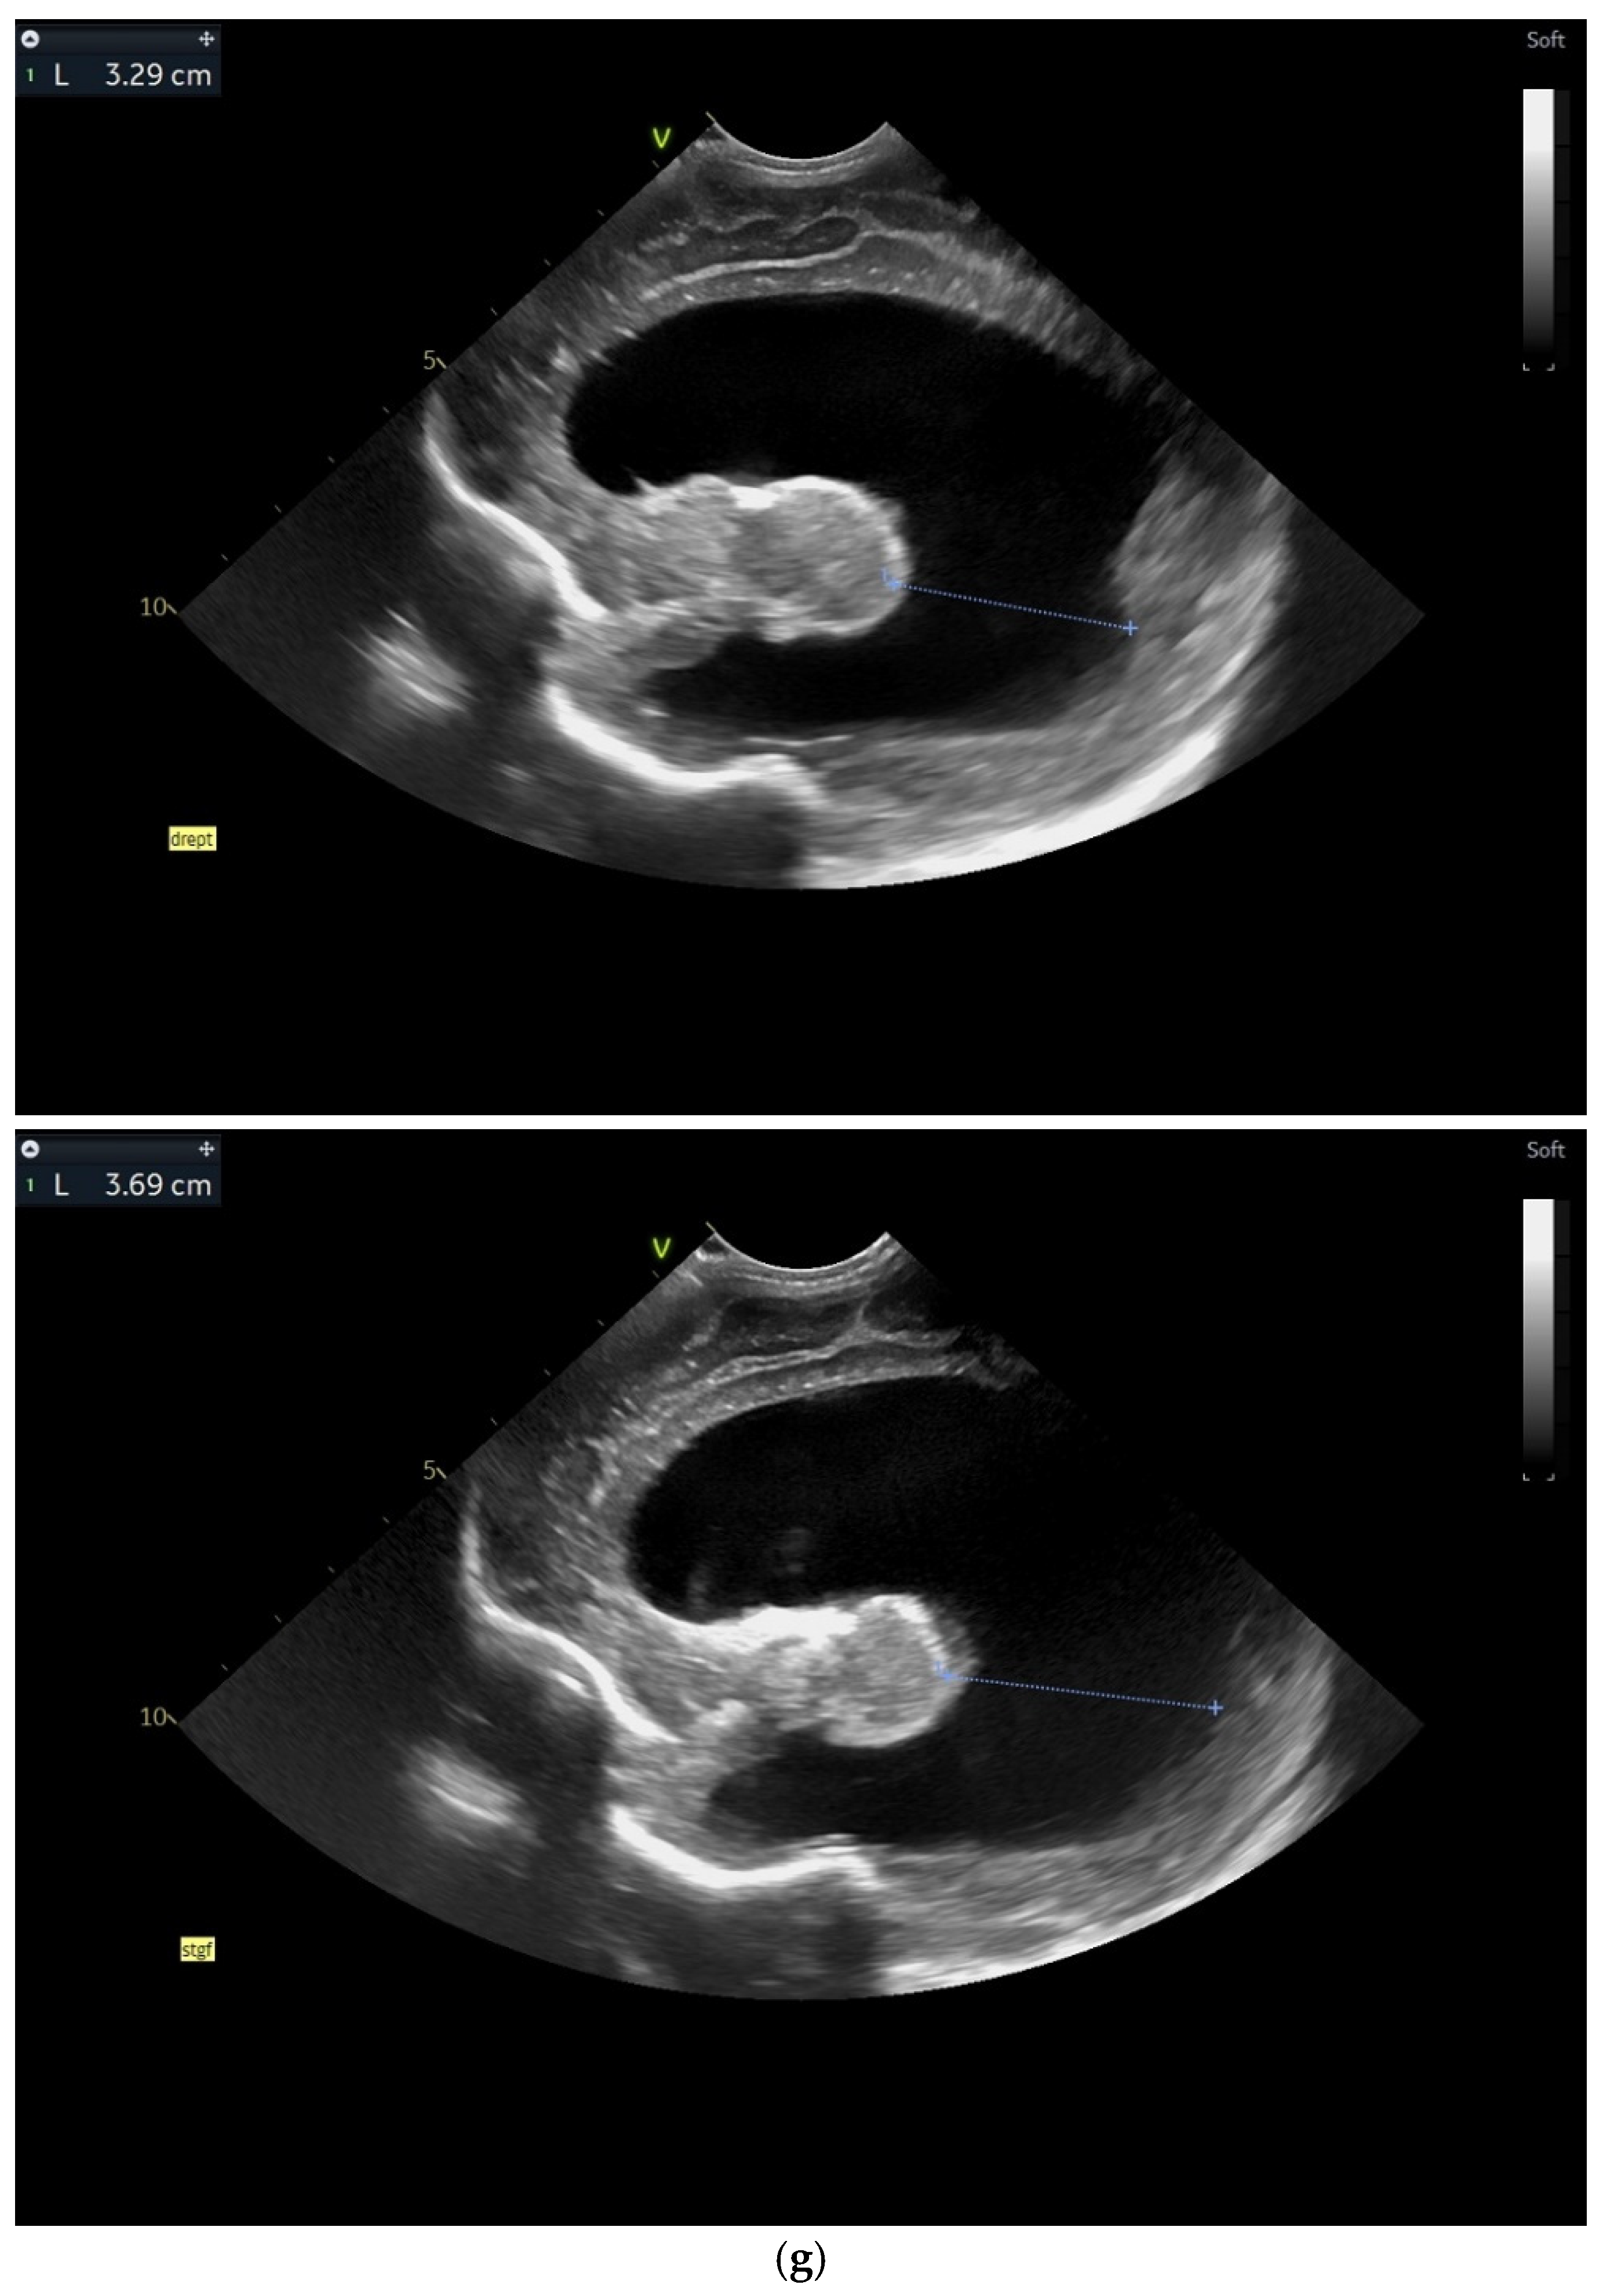

(a) Day one. Cranial ultrasound. Sagittal view. A left frontal conatal cyst can be observed. IHF—interhemispheric fissure. CG—cingulate gyrus. CC—corpus callosum. CSP—cavum septum pellucidum. TCG—thalamic-caudate groove. MF—Monroe foramina. SF—Sylvian fissure. Yellow arrow—conatal cyst (personal image collection). (b) Day three. Cranial ultrasound. Coronal view. Bilateral ventricular dilatation. Yellow arrows—hyperechoic images can be seen at the level of the thalamic-caudate groove and within the ventricles (personal image collection). (c) Day three. Cranial ultrasound. Coronal view. Orange arrows—bilateral periventricular hyperechoic images (personal image collection). (d) Day three. Cranial ultrasound—Doppler examination. Sagittal view. CC—corpus callosum. FL—frontal lobe. LV AH—lateral ventricle anterior horn. V 3—third ventricle. V 4—fourth ventricle. OL—occipital Lobe. Yellow arrow—presence of color Doppler signal within the Sylvian aqueduct (personal image collection). (e) Day 19. Cranial ultrasound. Sagittal view (left). Yellow arrows—conatal cysts. Pink arrows—PVL lesions (personal image collection). (f) Day 19. Cranial ultrasound. Sagittal view (left). Yellow arrows—conatal cysts. Pink arrows—PVL lesions (personal image collection). (g) Follow-up examination at term corrected age. Cranial ultrasound. Coronal view. Slight dilation of the lateral ventricles. IHF—interhemispheric fissure. CG—cingulate gyrus. CC—corpus callosum. CSP—cavum septum pellucidum. LV—lateral ventricle. MF—Monroe foramina (personal image collection). (h) Second follow-up examination. Cranial ultrasound. Coronal view. Dilation of interhemispheric fissure and subarachnoid space. D1—sinus–cortical width measurement. D2—interhemispheric width measurement. D3—cranio-cortical width measurement (personal image collection). (i) Third follow-up examination. Cranial ultrasound. Coronal view (left). D1—dilation of interhemispheric fissure. D2, D3—Levine index measurement (personal image collection). (j) Cranial ultrasound. Sagittal view (right). Normal brain structures (personal image collection). (k) Head circumference-for-age. “X” symbols represent the measurements performed from birth and follow-up examinations (personal image collection) [28].

On day three of life, the CUS displayed a bilateral germinal matrix hemorrhage with more than 50% of the ventricular volume being occupied by blood. Periventricular hyperechoic images could be observed as well (Figure 2b,c).

On the fourth day of life, a Doppler examination showed the presence of a signal within the third ventricle (Figure 2d).

A series of four lumbar punctures were performed during the patient’s in-stay to relieve the intracranial pressure—expressed as a bulging fontanelle. The first three lumbar punctures presented hemorrhagic CSF, while the last lumbar puncture showed sero-citrine CSF. Afterwards, the ventricular dimensions stabilized; however, small visible PVL lesions were visible on the CUS examination, in addition to the two conatal cysts that were observed (Figure 2e,f).

The first follow-up CUS examination was performed at the term-equivalent age (corrected gestational age) and revealed a slight dilation of the lateral ventricles (Figure 2g). The neurologic examination showed normal development for the corrected gestational age and mild plagiocephaly.

The next follow-up examination was performed two months from birth at the term-equivalent age and the CUS examination showed dilation of the interhemispheric fissure and the subarachnoid space (Figure 2h). Plagiocephaly, torticollis, mild motor development delay, and hypertonia in the lower limbs were observed.

Four months after the first follow-up examination, the CUS revealed normal brain structures. The general movement examination showed absent fidgety movements, while the neurological examination showed a global developmental delay with hypertonia of the limbs predominantly at the level of the left side of the body (Figure 2i,j).

On the fourth follow-up examination, the dilations were still visible. The neurological examination revealed mild trapezius muscle retraction and mild hypertonia at the level of the inferior limbs. The fifth follow-up examination—performed at one year after birth—revealed mild motor developmental delay.